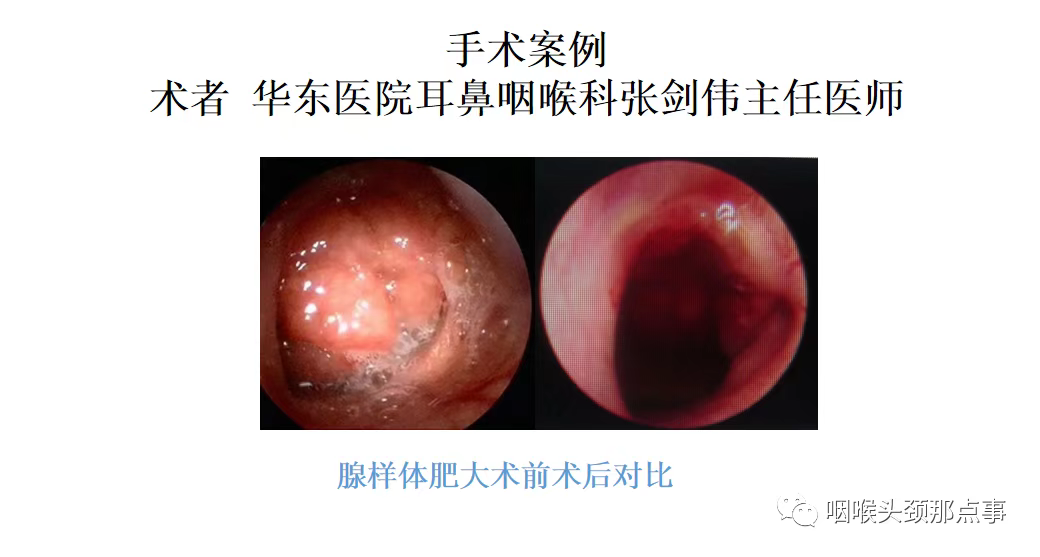

腺样体肥大

鼻咽部儿童常见的就是腺样体肥大,少见的鼻咽纤维血管瘤,常见于青少年及年轻男性,还有就是鼻咽部恶性肿瘤。